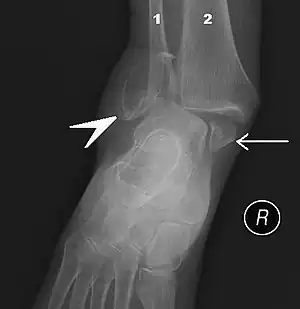

Ankle fractures may result from excessive stress on the joint such as from rolling an ankle or from blunt trauma.[20][21] Types of ankle fractures include lateral malleolus, medial malleolus, posterior malleolus, bimalleolar, and trimalleolar fractures.[20] The Ottawa ankle rule can help determine the need for X-rays.[21] Special X-ray views called stress views help determine whether an ankle fracture is unstable.

Ankle fractures are common, occurring in over 1.8 per 1000 adults and 1 per 1000 children per year.[21][22] They occur most commonly in young males and older females.[21]Imaging

The initial evaluation of suspected ankle pathology is usually by projectional radiography ("X-ray").

Varus or valgus deformity, if suspected, can be measured with the frontal tibiotalar surface angle (TTS), formed by the mid-longitudinal tibial axis (such as through a line bisecting the tibia at 8 and 13 cm above the tibial plafond) and the talar surface.[23] An angle of less than 84 degrees is regarded as talipes varus, and an angle of more than 94 degrees is regarded as talipes valgus.[24]

For ligamentous injury, there are three main landmarks on X-rays: The first is the tibiofibular clear space, the horizontal distance from the lateral border of the posterior tibial malleolus to the medial border of the fibula, with greater than 5 mm being abnormal. The second is tibiofibular overlap, the horizontal distance between the medial border of the fibula and the lateral border of the anterior tibial prominence, with less than 10 mm being abnormal. The final measurement is the medial clear space, the distance between the lateral aspect of the medial malleolus and the medial border of the talus at the level of the talar dome, with a measurement greater than 4 mm being abnormal. Loss of any of these normal anatomic spaces can indirectly reflect ligamentous injury or occult fracture, and can be followed by MRI or CT.[25]